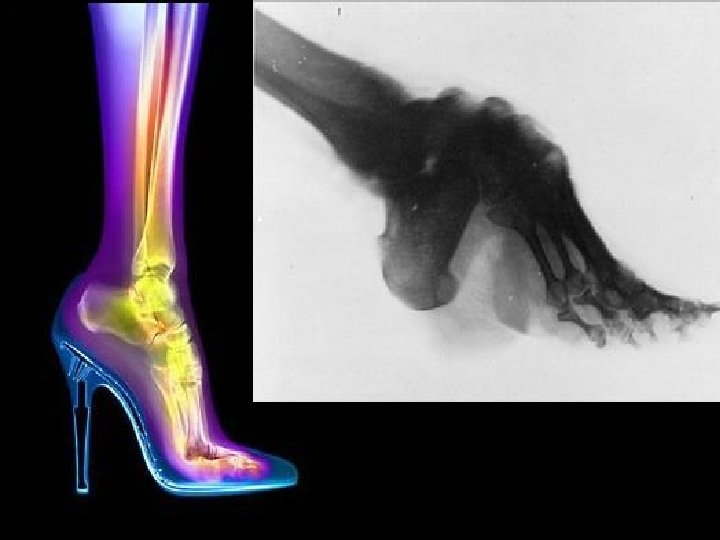

CASOS PATOLÓGICOS DEL PIE EQUINOVARO PIE EQUINO Está producido por la parálisis de los músculos dorsales del pie. Para tratarlos; relajación de los Flexores plantares y estimular los Tibiales y Peroneales. Ref. pág. 7 Se produce por la parálisis de los músculos Peroneos. Relajar Tibiales y fortalecer Peroneales.

CASOS PATOLÓGICOS DEL PIE CALCÁNEO Está producido por la parálisis de los músculos Flexores Plantares. Fortalecer Flexores y relajar Tibiales y Peroneales. Ref. pág. 7 PIE PLANO Está producido por la parálisis del Flexor Largo del dedo gordo. Utilización de plantillas Ortopédicas. HALLUX VALGUS Está producido por una lesión de uno de los músculos cortos del pie. Utilización de (Ortesis Falángicas)